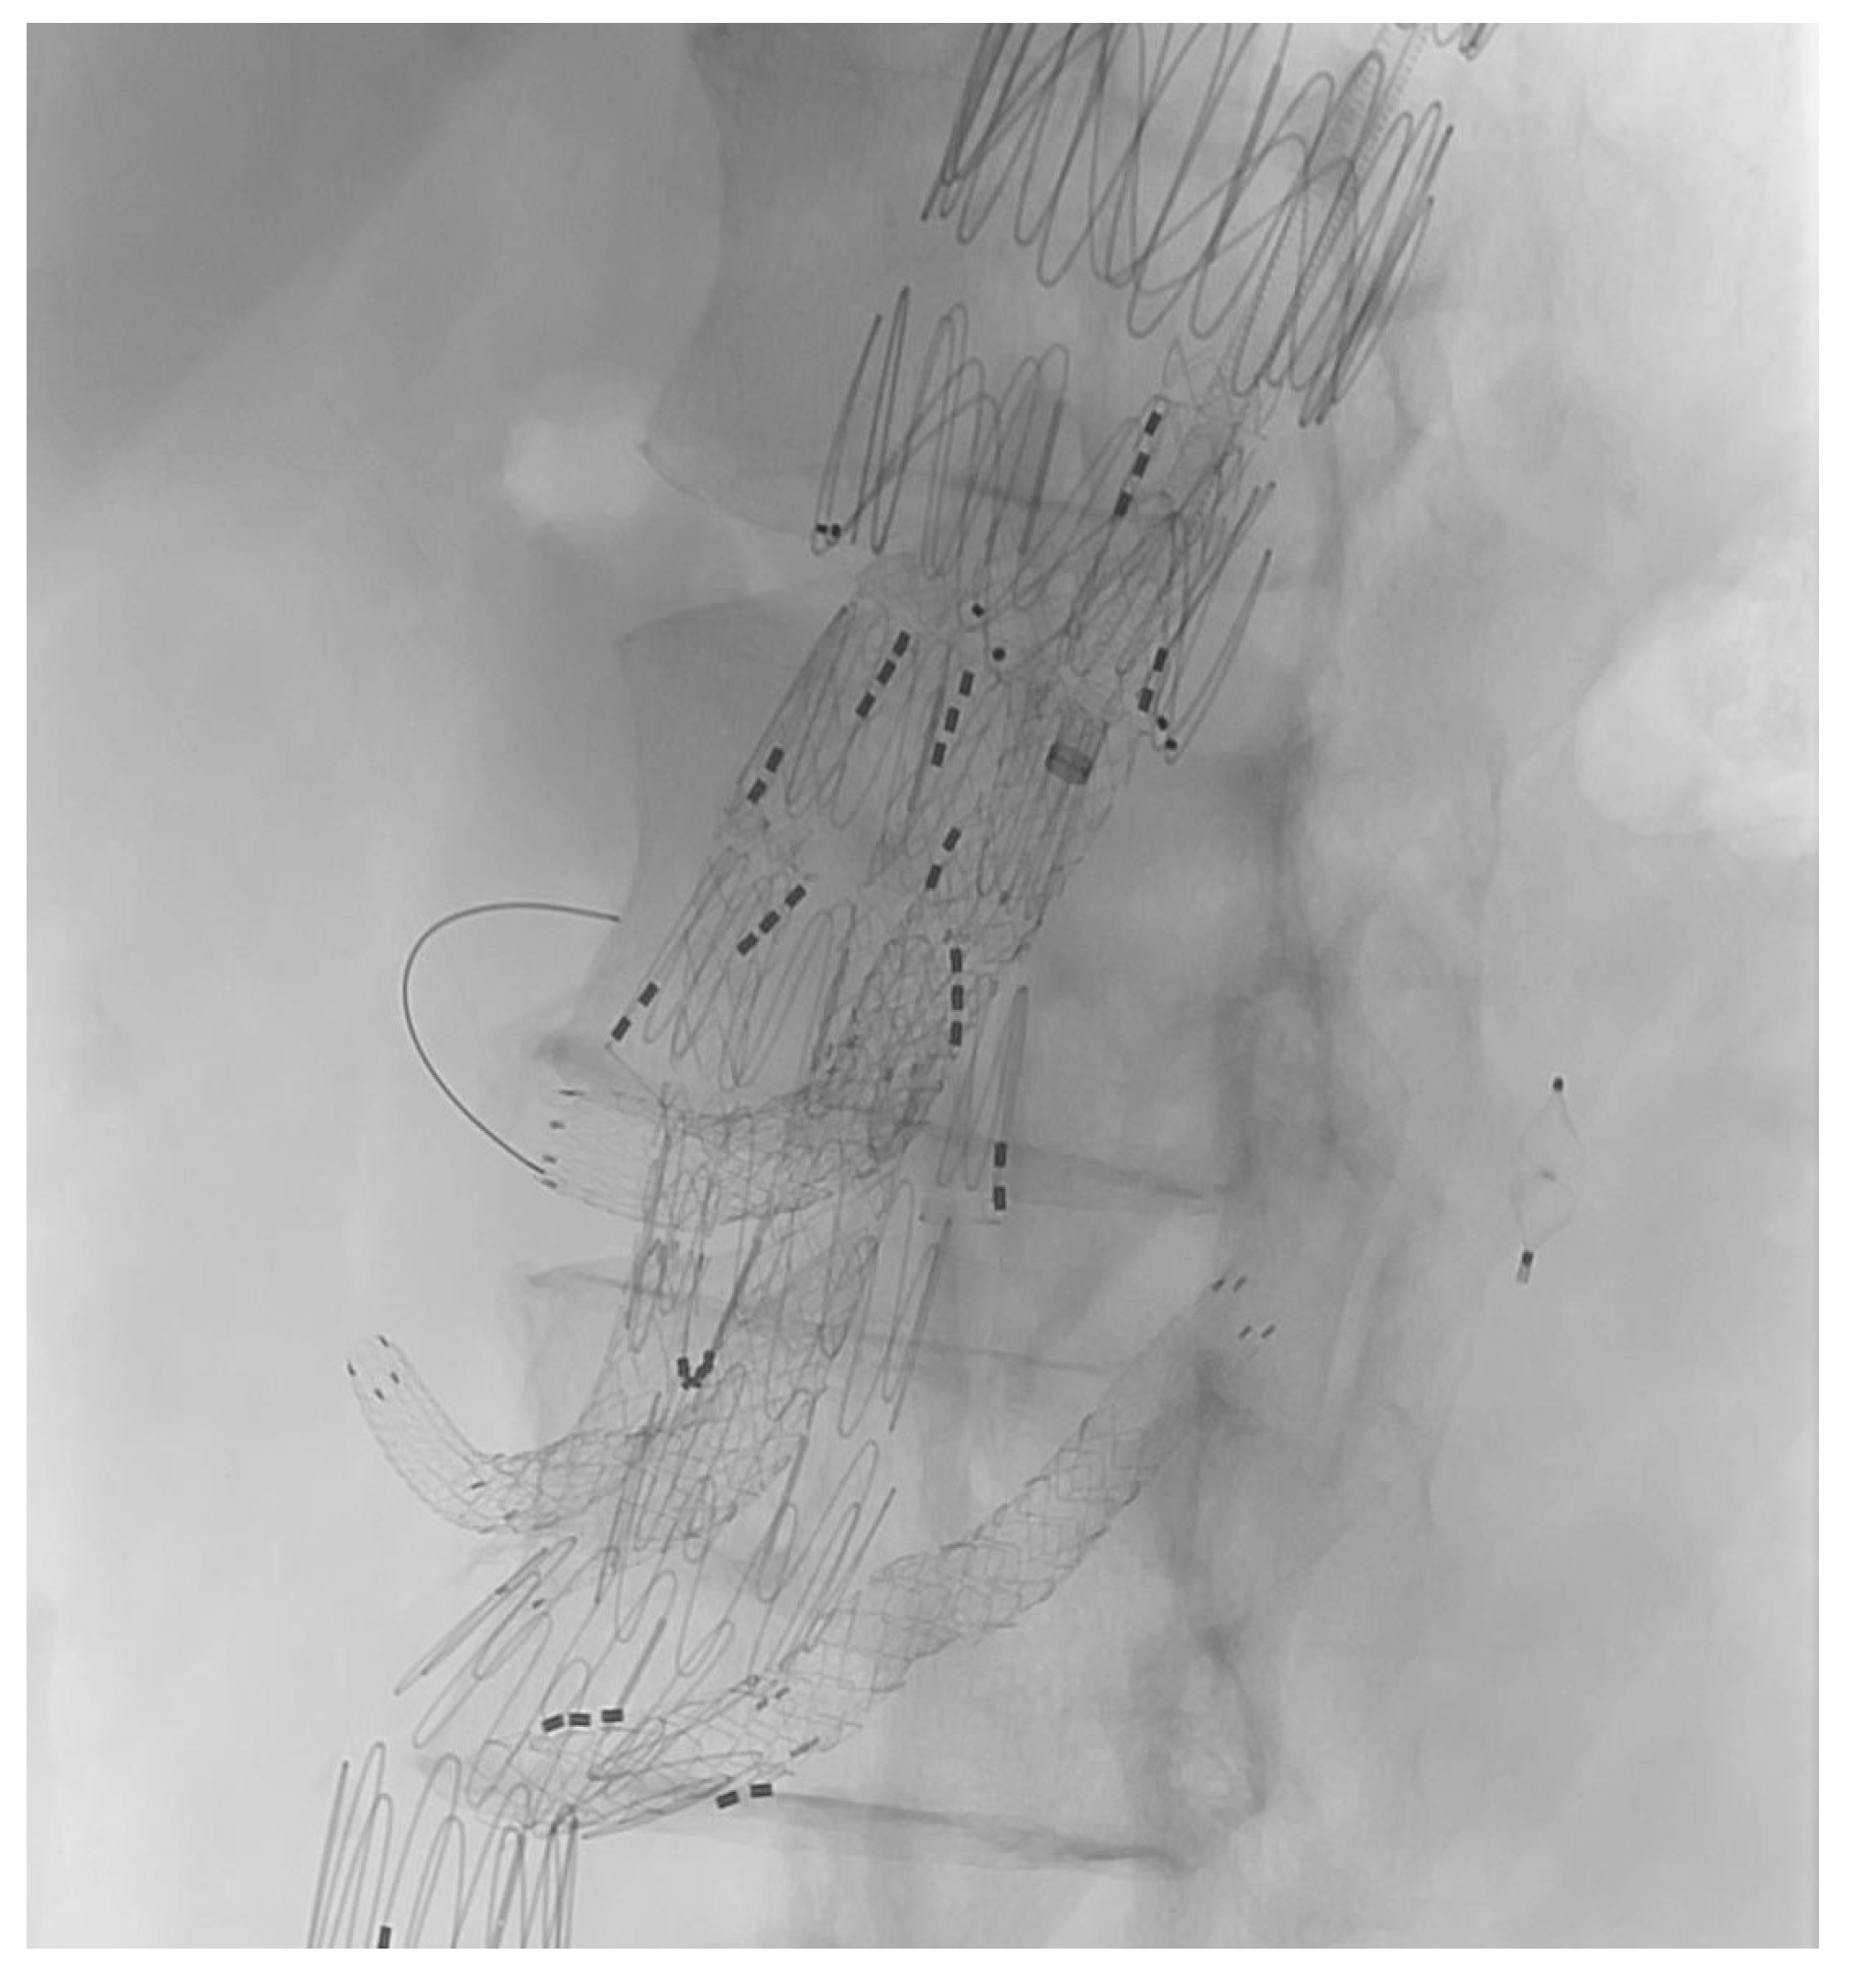

At the end of every operation, an angiography was performed to obtain an overview regarding if the BSGs are patent and if there is any sign of an endoleak of any type (Figure 3 and Figure 4).

Figure 3. Upward-facing branch for the LRA.